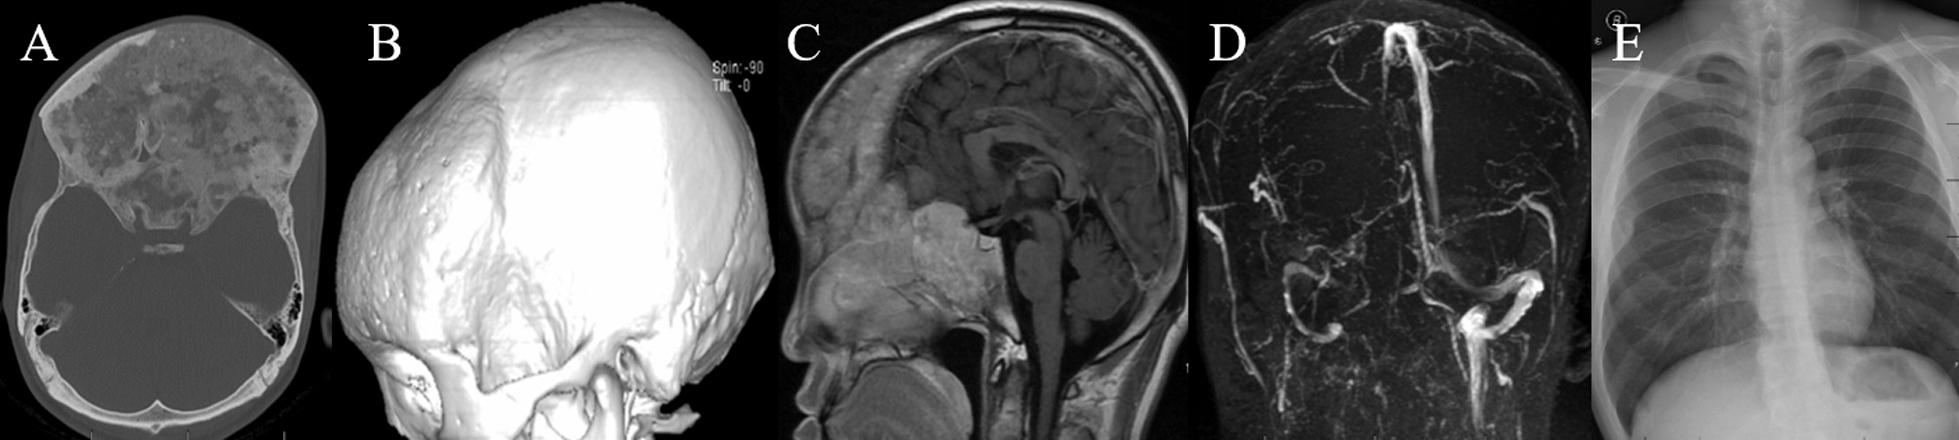

22 out of 1175 patients (1.9%) were diagnosed with craniofacial fibrous dysplasia and cerebrovascular diseases including 9 intracranial aneurysms, 4 venous malformations, 2 arteriovenous malformations, 1 moyamoya disease, 2 intracranial venous stenosis and 4 cerebral ischemia with a mean age of 38.18 years old. Only 2 patients were managed surgically for craniofacial fibrous dysplasia and 6 patients were treated with neurosurgery for cerebrovascular diseases. 8 patients were closely followed and only 1 patient's symptoms worsened.

1175例患者中有22例(1.9%)被诊断为颅面骨纤维发育不良合并脑血管疾病,包括9例颅内动脉瘤、4例静脉畸形、2例动静脉畸形、1例烟雾病、2例颅内静脉狭窄和4例脑缺血,平均年龄为38.18岁。仅2例患者因颅面骨纤维发育不良接受了手术治疗,6例患者因脑血管疾病接受了神经外科治疗。8例患者进行了密切随访,只有1例患者症状加重。